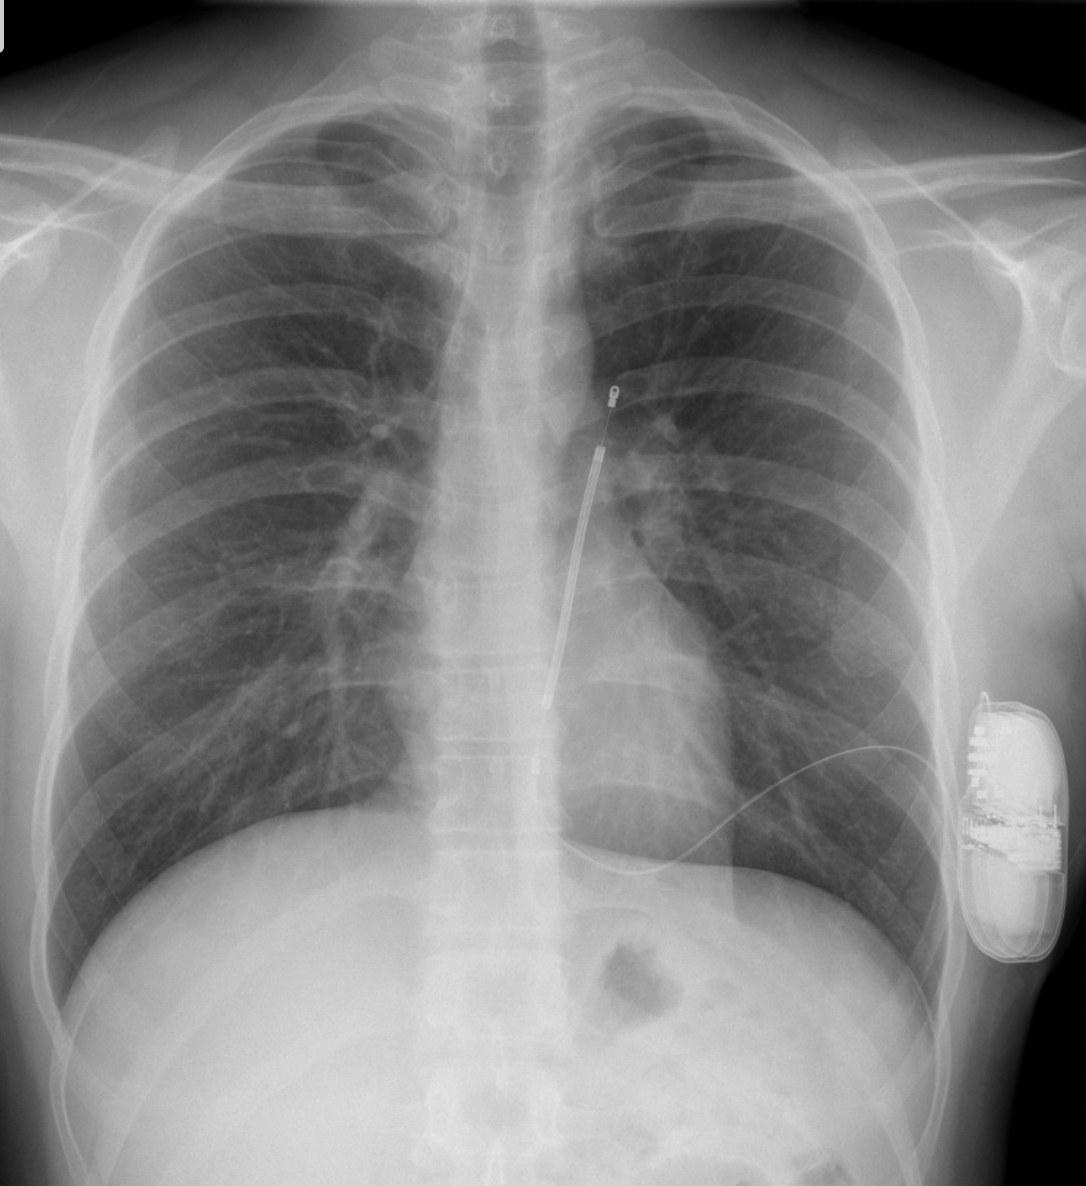

-Implantable Loop Recorder